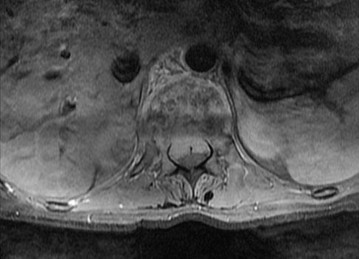

A 28-year-old male presents after a diving accident. He is awake and alert, complaining of severe neck pain. Neurological exam reveals 4/5 strength in right elbow flexion and wrist extension, with numbness extending into the thumb. Radiographs are obtained showing a unilateral facet dislocation.

If an awake closed reduction is attempted but fails, what is the most appropriate next step in management?

Explanation

In an awake, cooperative patient with a cervical facet dislocation, closed reduction via cranial traction may be attempted prior to MRI. However, if closed reduction fails, an MRI MUST be obtained prior to any open reduction to evaluate for a herniated nucleus pulposus. If a herniated disc is present, an anterior approach is necessary to decompress the spinal cord before the facet joint is reduced, mitigating the risk of devastating iatrogenic spinal cord injury.